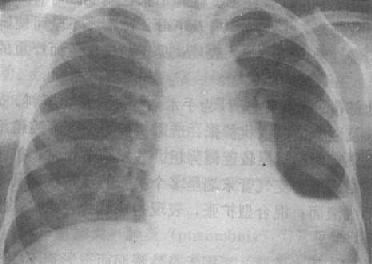

粟粒型肺结核病灶小,透视常难以辩认,故拟诊急性粟型肺结核时应摄片检查。病变早期整个肺野可呈毛玻璃样密度增高。约10日后可出现均匀分布的1.5~2mm大小、密度相同的粟粒状病灶,正常肺纹理常不能显示(图3-1-22)。经过适当治疗后。病灶可在数月内逐渐吸收,偶尔以纤维硬结或钙化而愈合。病变恶化时,可以发生病灶融合,表现为病灶增大,边缘模糊,甚至形成小片状或大片状影,并可干酪样化而形成空洞。

图3-1-22 急性粟粒型肺结核

两肺野布满粟粒状病灶,分布均匀,肺门大